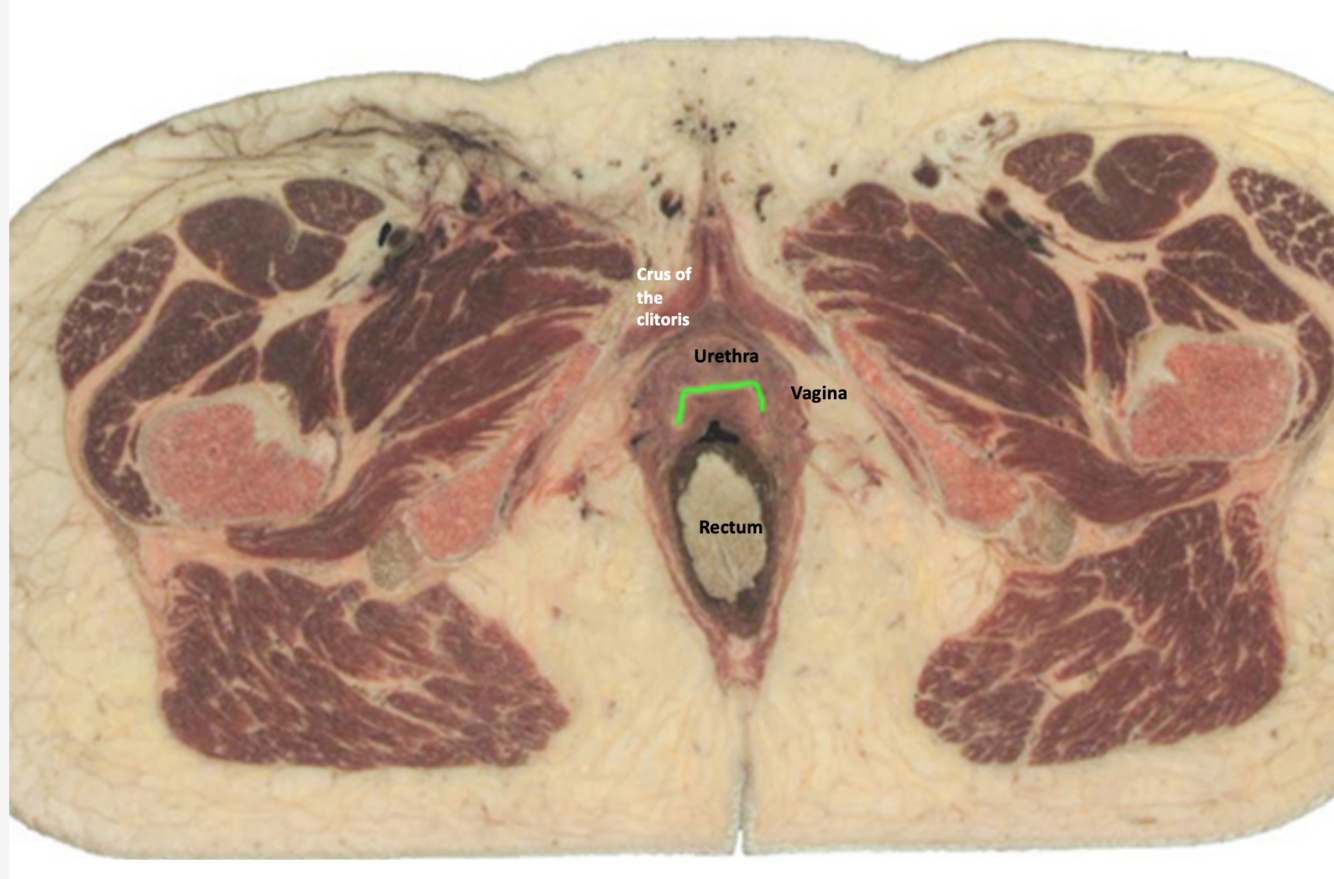

What muscle is responsible for clitoral errection?

bulbocavernous & ischiocavernosus

What muscle is pinned?

Ischiocavernosum